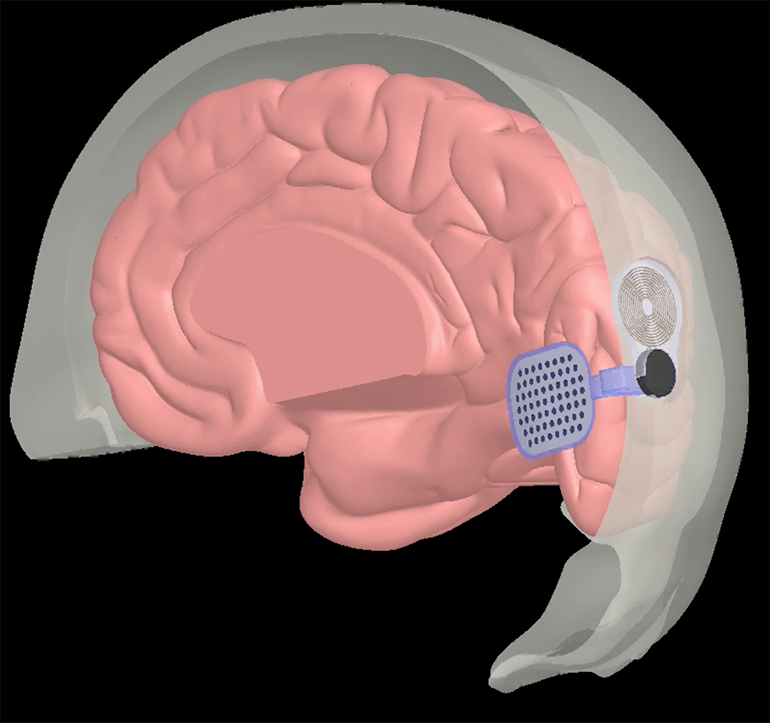

Nader Pouratian презентував проміжні результати раннього дослідження системи кортикального зорового протезу Orion (Second Sight Medical Products). Імплантат було встановлено шести пацієнтам. Він напряму стимулює зорову кору, оминаючи очі та зорові шляхи. Сам імплантат отримує сигнал від спеціальної камери, що розташований на окулярах, які носить пацієнт. Камера фіксує зображення в режимі реального часу, які обробляються VPU, а потім перетворюються на патерни стимуляції, які через бездротовий зв’язок передаються до електродів, імплантованих в зорову кору. В дослідження були включені пацієнти, які раніше мали здатність бачити, але втратили зір через причини, які не включали ураження зорової кори.

Схема принципу роботи системи Orion